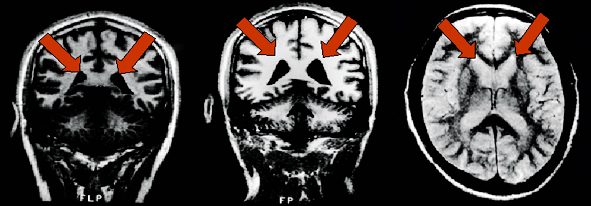

Programa de Investigación, Trastornos del Humor, encontraron que la amígdala parece ser ampliada significativamente en pacientes con enfermedad bipolar, junto con dilatación de los ventrículos.(Foto © UCLA).

De izquierda a derecha: vista de un cerebro normal, el paciente con trastorno bipolar tiene dilatación de los ventrículos, manchas de color blanco brillante de hiperintensidad asociados con la enfermedad bipolar.

La amígdala izquierda (zona amarilla, donde las líneas se cruzan) y las estructuras relacionadas forman parte de un circuito cerebral que regula la emoción donde los niños con trastorno bipolar mostraron una mayor activación que los controles en la calificación de temor ante rostros neutrales. Estructura de la imagen con resonancia magnética funcional MRI datos superpuestos.